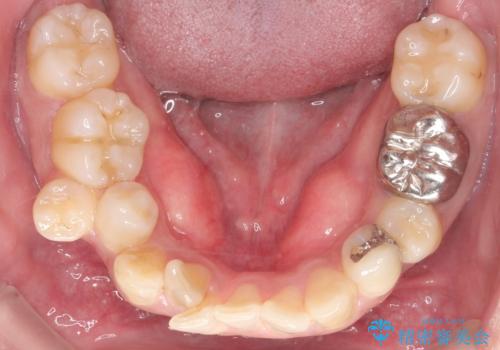

重度の叢生を抜歯矯正で改善|審美ワイヤー矯正+海外出張に伴う中断・再開対応

- 治療計画

重度の叢生により、抜歯を伴う矯正が必要と判断しました。目立ちにくい透明な審美ブラケットを用いたワイヤー矯正を実施しましたが、治療途中での海外出張が決定したため、一度矯正装置を取り外し、保定装置で現状維持を行いました。帰国後に改めて装置を装着し矯正を再開。患者様のライフスタイルに柔軟に対応しながら、最終的には理想的な歯並びと美しい口元を実現しました。